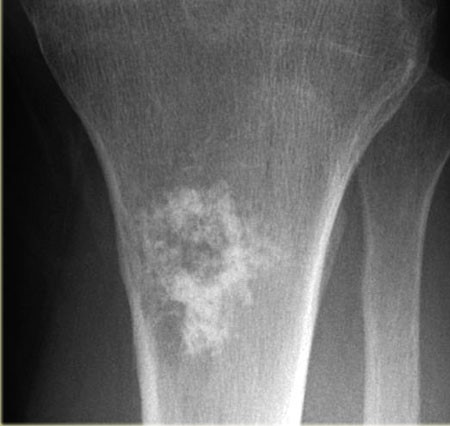

Рак Костей Симптомы И Проявление Фото

Рак Костей Симптомы И Проявление Фото 115 фото